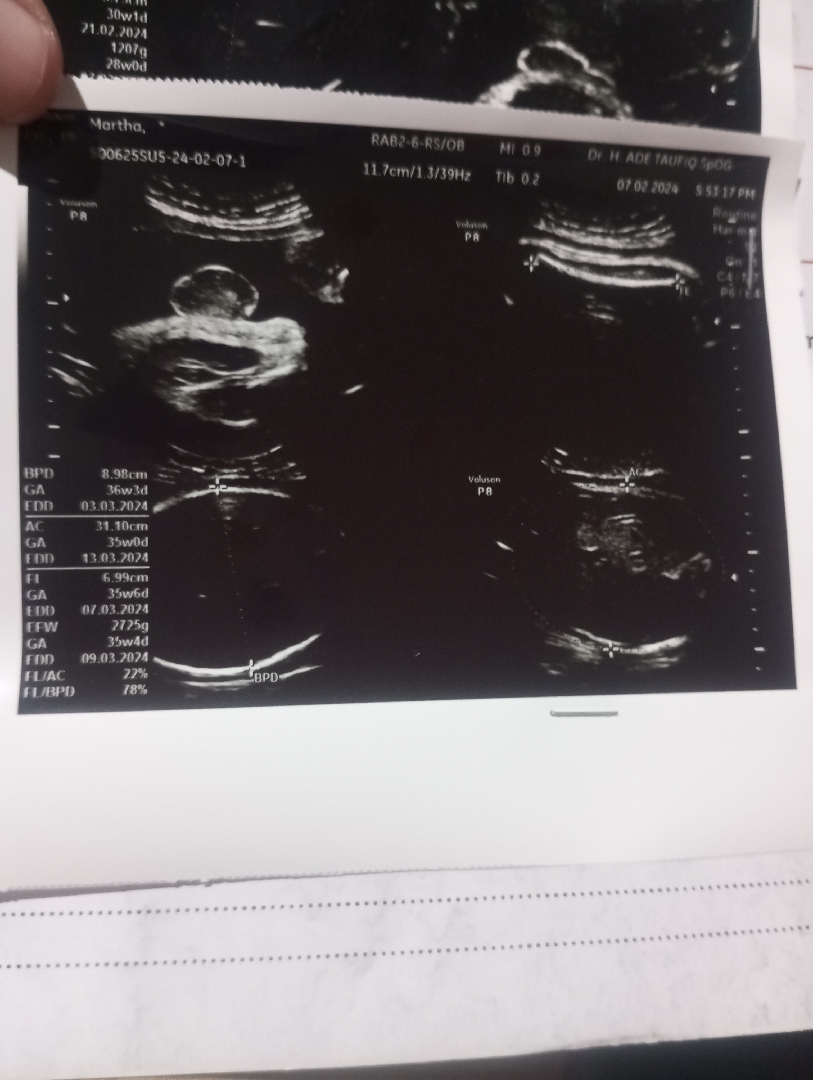

Di bln Desember usia kandunganku 7 bln di USG kata dokter sungsang bun.. Smpai periksa ke bidan jg di bln 1 nya sungsang.. Tp aku tetap ga nyerah.. Ku perbanyak wktu buat sujud2(nungging) gtu bun..Puji Tuhan,di bln febuari saya USG lg td, si dedeknya udah ke posisi yg benar, kepala udah di bawah. . Ga sungsang lg bun.. Oh ia buat para bunda yg posisi debay nya msh sungsang tetap semangat yaaa 😊😊 sering2 sujud dlm wktu yg lama.. Debay nya di ajak curhat bun.. Kaya di bujuk gt ga lupa jg di barengin dgn doa. Mudah2 bisa posisi normal. Semngat ya bun.... 🙂